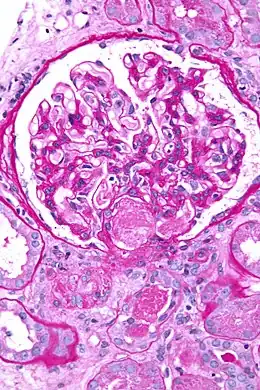

La coagulation intravasculaire disséminée (CIVD), aussi appelée syndrome de défibrination ou coagulopathie de consommation, est une activation pathologique de la coagulation (formation de caillots sanguins). Elle apparaît dans de nombreuses situations pathologiques quand de petits caillots se forment dans les vaisseaux sanguins de tout l'organisme[1]. Ces caillots consomment les facteurs de coagulation. La coagulation normale est ainsi empêchée et des hémorragies (saignements) anormales apparaissent sur la peau (notamment aux sites de prélèvements sanguins), le tube digestif, le tractus respiratoire et les cicatrices chirurgicales. Les petits caillots perturbent aussi le flux sanguin vers les organes (comme les reins) et entraînent une perturbation de leur fonctionnement[2].

- phénomènes thrombotiques : oblitération des petits vaisseaux ;

- des manifestations thrombotiques : thromboses veineuses profondes, infarctus viscéraux, purpura nécrotique, gangrènes distales ;